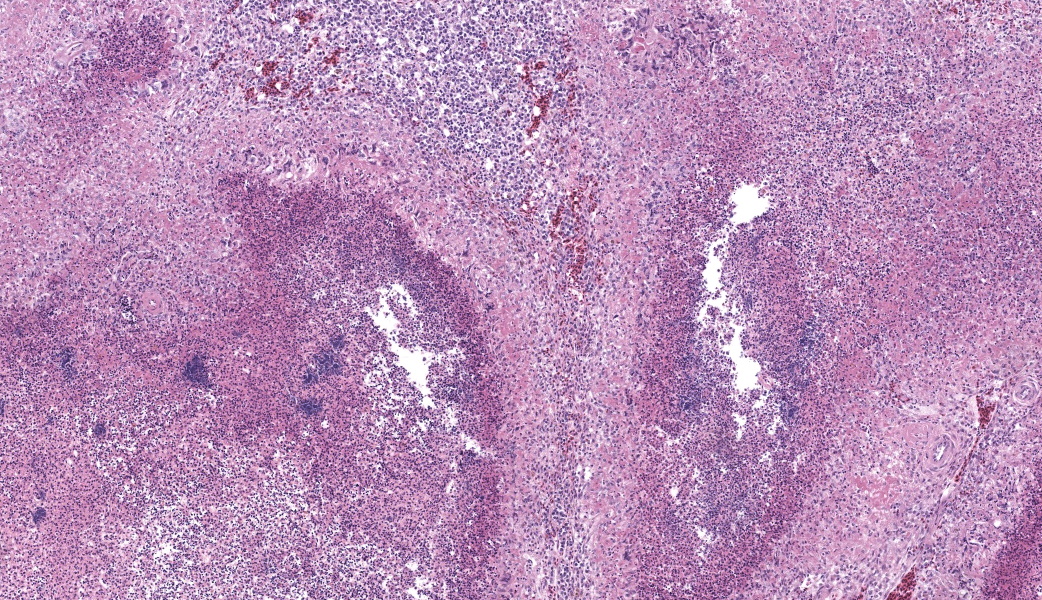

Microscopic Description:

Liver: Three sections of liver are examined. Within one section, there are multiple and coalescent, irregularly shaped granulomas replacing up to 60% of the tissue, multifocally blending in with the fibrous connective tissue of portal areas. Granulomas center around hypereosinophilic necrotic material mixed with relatively low to medium numbers of degenerate heterophils and cellular debris and multiple clusters of coccoid bacteria. Bordering the necrotic center is a layer of palisading macrophages with abundant eosinophilic and frequently vacuolated cytoplasm (epithelioid macrophages) and occasional multinucleated giant cells, which are further outlined by a robust layer of fibroblasts and collagen. Portal areas are variably expanded by medium to high numbers of lymphocytes, plasma cells, macrophages, including many laden with brown cytoplasmic granules, intermingled with numerous bile ducts (biliary hyperplasia), which extend into the adjacent parenchyma. In some portal areas, there are higher numbers of granulocytes with large, indented, vesiculate nuclei (interpreted as myeloid precursor cells and extramedullary hematopoiesis). Throughout all three sections of liver are individual necrotic hepatocytes to large regions of coagulative necrosis often centered around centrilobular veins, characterized by hepatocytes with shrunken, angular cell borders, hypereosinophilic cytoplasm and a pyknotic to karyorrhectic nucleus; larger areas of coagulative necrosis are frequently infiltrated by viable and non-viable heterophils. Within areas of necrosis and areas of viable hepatocytes are small clusters of coccoid bacteria within sinusoids.Spleen: The splenic parenchyma is interrupted by a few, relatively smaller, coalescing granulomas centered around numerous viable and non-viable heterophils, pyknotic nuclei and cellular and karyorrhectic debris, which is separated by a collar of collagen and macrophages with the occasional multinucleated giant cells. Within these regions, there are multifocal cocci bacteria colonies. There are deposits of fibrin and serum protein present throughout the sinuses and around ellipsoids. Within these foci are few reticuloendothelial cells, red cells, low numbers of lymphocytes and macrophages, as well as pyknotic nuclei and karyorrhectic and cellular debris and colonies of coccoid bacteria.

Liver: granulomatous and necrotizing hepatitis, multifocal to coalescing, severe, with intralesional cocci and biliary hyperplasiaSpleen: granulomas, multifocal, marked, with intralesional and embolic cocci

- Spleen: Splenitis, necrotizing, heterophilic and granulomatous, chronic, multifocal, moderate, with numerous cocci.

The University of Pennsylvania's Dr. Nathan Helgert moderated this year's 11th conference. This is his first time moderating for the WSC, and participants thoroughly enjoyed his quick wit and engaged teaching style. He chose to focus on poultry and ruminant pathology, which participants are always grateful for. This first case was a classic entity with fantastic histologic lesions that, according to some conference goers, provided the perfect moment to make use of the term "geographic" to describe those dramatic areas of necrosis. They truly resemble some beautiful cartography.Conference discussion focused on the diagnostic approach to cases like this one where additional diagnostics are required to "suss out" the etiologic agent. Participants were asked to take a figurative step back and develop a list of possible causes of bacterial sepsis in chickens that could lead to hepatic and splenic lesions like these. The list included E. coli (colibacillosis), Salmonella typhimurium, Staphylococcus aureus, Enterococcus spp, Streptococcus spp.,Erysipelothrix rhusiopathiae (although this is more likely in turkeys and pheasants than in chickens), Mycobacterium spp (especially M. avium), and Pasteurella multocida, to name just a few. Some of these look nearly identical to one another both grossly and histologically, while others of these have more distinct features. Either way, culture and special stains will be needed.